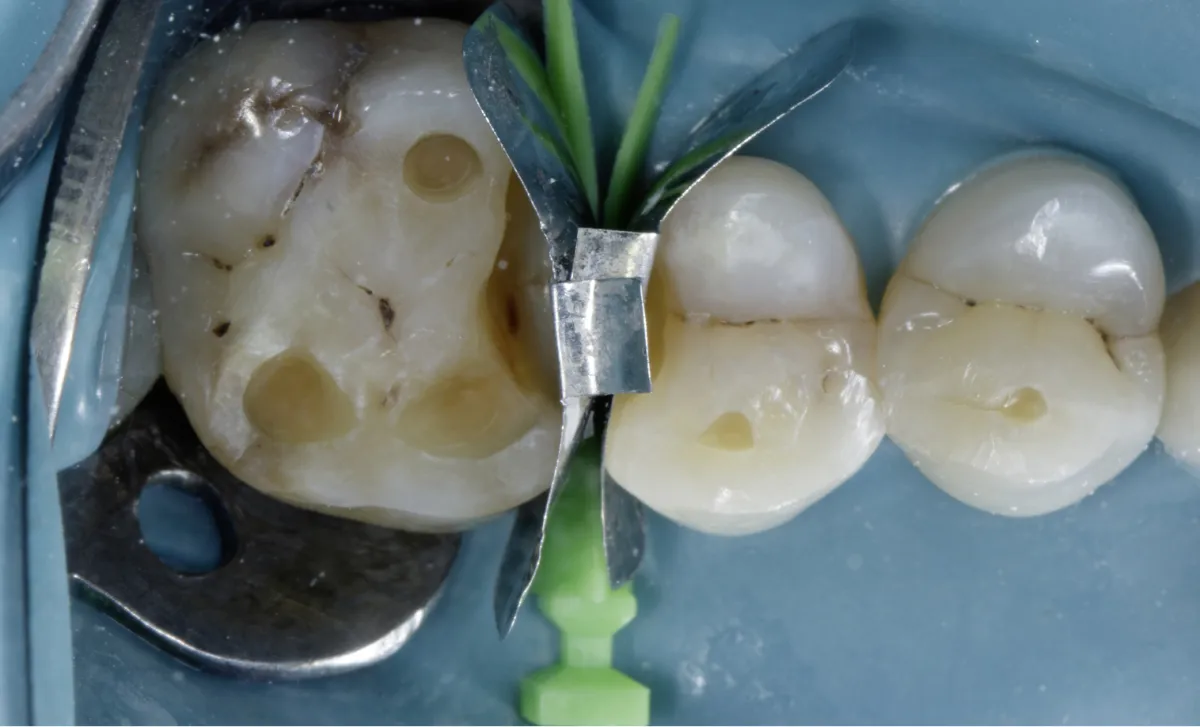

The first band (FXH 200) was placed in the distal defect of tooth #15 and secured using a Large Quad Wedge (Figure 05).

Next, an identical band was inserted into the mesial defect of tooth #16 by slightly repositioning the wedge, allowing the band to pass beneath it. The wedge was then reinserted to its full length, holding the bands in place with gentle finger pressure, ensuring both bands were securely positioned beneath the wedge. (Figure 05)

Figure 05: The FXH 200 band was securely positioned using a Large Quad Wedge placed from Buccal, ensuring a tight seal.

Due to the larger defect on the palatal side compared to the buccal, we inserted the Quad large wedge from the palatal. The unique design of the wedge, with its broader area, ensures that the band is securely positioned at the wider defect, eliminating any gaps at the gingival seat area. (Figure 08)

Once the band is securely in place, the Quad ring is selected and positioned with its driver tip on the buccal side, following the placement of the wedge from the palatal. Teflon tape is then placed inside the defect to shape the band to the adjacent tooth, ensuring ideal contour and contact. (Figure 09)